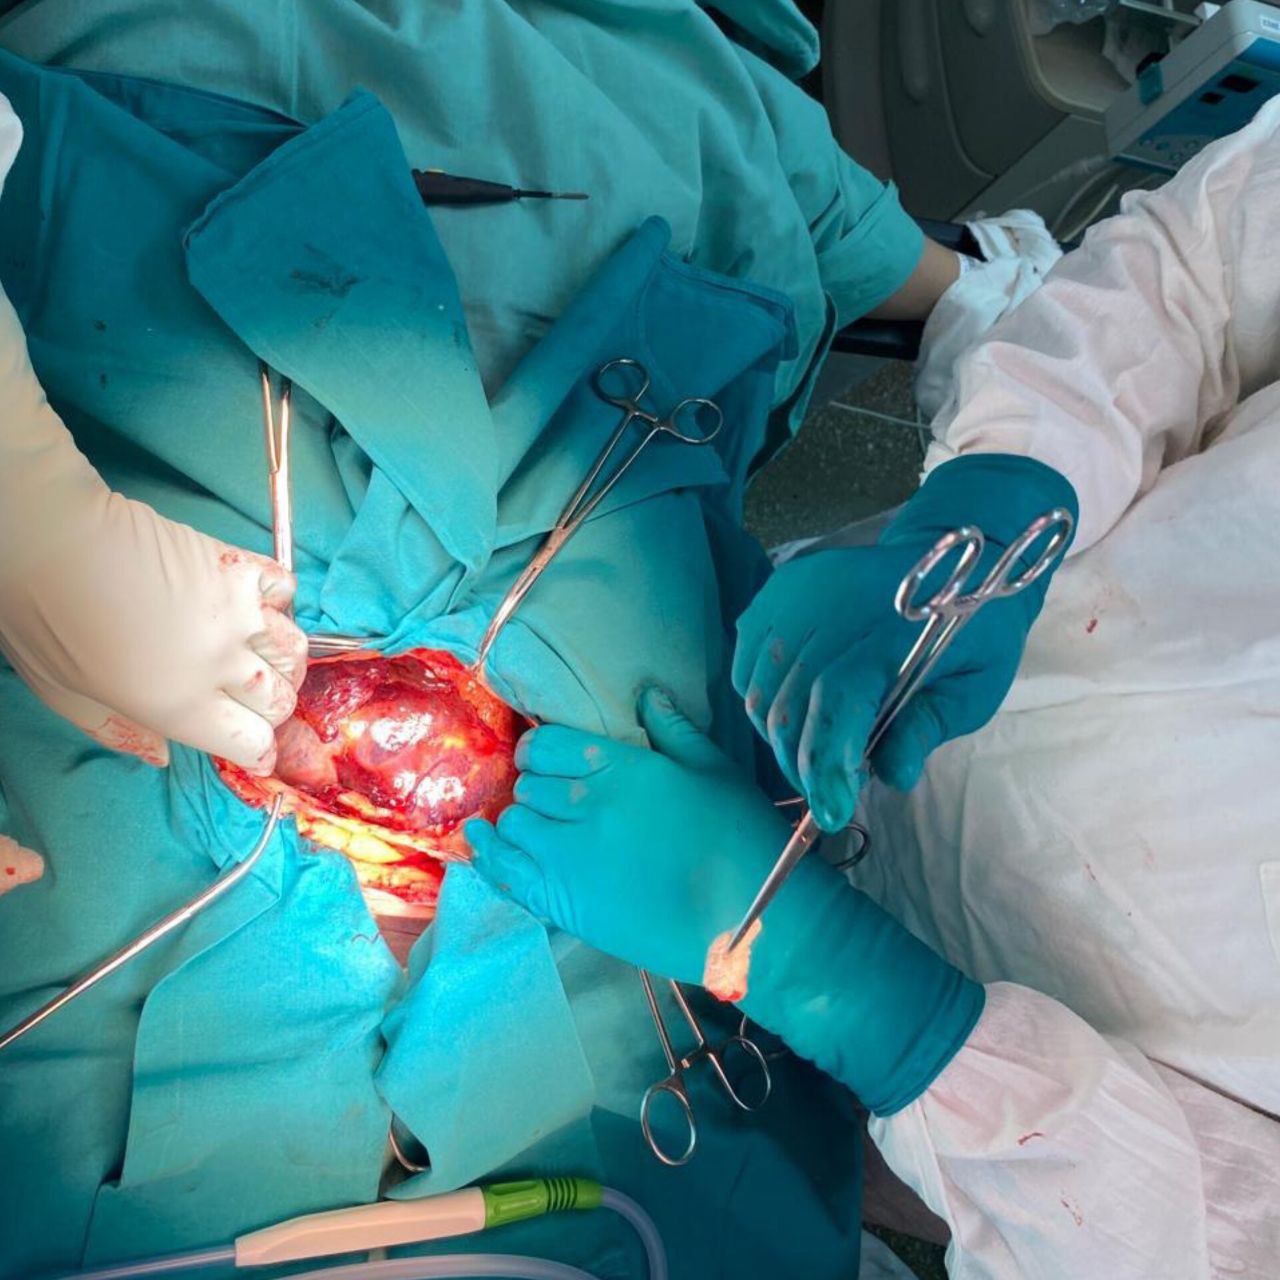

Врачи Больницы на Кутузова удалили пациентке цистаденому яичника гигантских размеров

Специалисты Больницы на Кутузова удалили 84-летней пациентке опухолевидное образование 30 см в диаметре

Командная работа врачей КГБУЗ "КМКБ № 4" по удалению редкой патологии